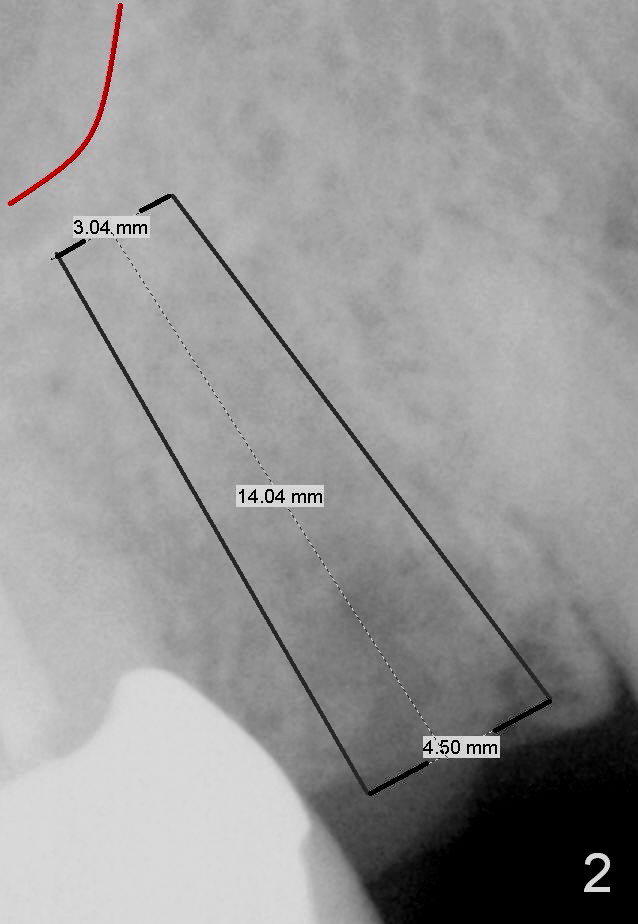

A 55-year-old lady had the tooth #4 extracted with socket preservation 4-5 months ago. The ridge does not look too narrow. Use a 3 mm tissue punch from the DIO 1 piece implant kit for access. Also prepare #15 blade. Since bone density within the healing socket seems low (Fig.1), use bone expanders, until 2-3 sizes smaller than the designed implant (4.5x14 mm, Fig.2). Pilot drill at 10 mm and take PA. After using the last bone expander, taken another PA. What is the real reason using bone expanders in this case, since the ridge is not so narrow?